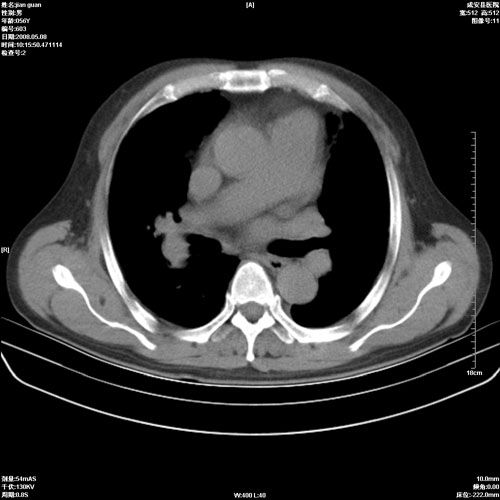

病人 男 60岁 主诉 胸闷 无明显发热 一般情况尚可。

考虑1心功不全,肺水肿

2右上肺结核纤维性病灶、肺气肿

1.右上肺陈旧性肺结核.

2.心脏增大(以左心室增大为著),请结合b超及听诊.

1.两上肺陈旧性结核;慢支肺气肿。

2.肺门血管扩张,心脏增大,为肺心病

考虑.两上肺陈旧性结核;慢支肺气肿。肺心病

1.陈旧肺结核;

2.慢支肺气肿;

3.肺心病.

陈旧性肺结核,左心房扩大,左心衰竭

2右上肺结核纤维性病灶、肺气肿 ,肺心病